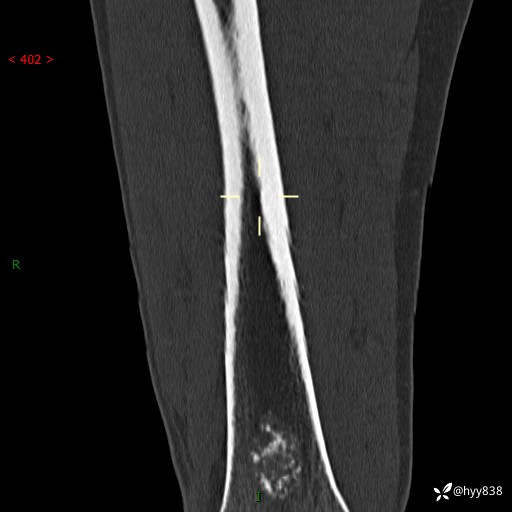

CT

img